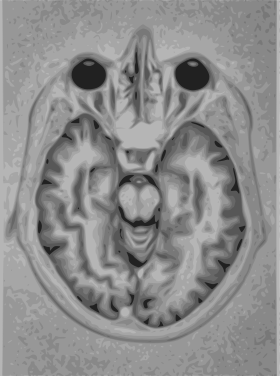

A magnetic resonance imaging instrument (MRI scanner), or "nuclear magnetic resonance (NMR) imaging" scanner as it was originally known, uses powerful magnets to polarize and excite hydrogen nuclei (i.e., single protons) of water molecules in human tissue, producing a detectable signal which is spatially encoded, resulting in images of the body.[4] The MRI machine emits a radio frequency (RF) pulse at the resonant frequency of the hydrogen atoms on water molecules. Radio frequency antennas ("RF coils") send the pulse to the area of the body to be examined. The RF pulse is absorbed by protons, causing their direction with respect to the primary magnetic field to change. When the RF pulse is turned off, the protons "relax" back to alignment with the primary magnet and emit radio-waves in the process. This radio-frequency emission from the hydrogen-atoms on water is what is detected and reconstructed into an image. The resonant frequency of a spinning magnetic dipole (of which protons are one example) is called the Larmor frequency and is determined by the strength of the main magnetic field and the chemical environment of the nuclei of interest. MRI uses three electromagnetic fields: a very strong (typically 1.5 to 3 teslas) static magnetic field to polarize the hydrogen nuclei, called the primary field; gradient fields that can be modified to vary in space and time (on the order of 1 kHz) for spatial encoding, often simply called gradients; and a spatially homogeneous radio-frequency (RF) field for manipulation of the hydrogen nuclei to produce measurable signals, collected through an RF antenna.

Like CT, MRI traditionally creates a two dimensional image of a thin "slice" of the body and is therefore considered a tomographic imaging technique. Modern MRI instruments are capable of producing images in the form of 3D blocks, which may be considered a generalization of the single-slice, tomographic, concept. Unlike CT, MRI does not involve the use of ionizing radiation and is therefore not associated with the same health hazards. For example, because MRI has only been in use since the early 1980s, there are no known long-term effects of exposure to strong static fields (this is the subject of some debate; see 'Safety' in MRI) and therefore there is no limit to the number of scans to which an individual can be subjected, in contrast with X-ray and CT. However, there are well-identified health risks associated with tissue heating from exposure to the RF field and the presence of implanted devices in the body, such as pace makers. These risks are strictly controlled as part of the design of the instrument and the scanning protocols used.

Because CT and MRI are sensitive to different tissue properties, the appearance of the images obtained with the two techniques differ markedly. In CT, X-rays must be blocked by some form of dense tissue to create an image, so the image quality when looking at soft tissues will be poor. In MRI, while any nucleus with a net nuclear spin can be used, the proton of the hydrogen atom remains the most widely used, especially in the clinical setting, because it is so ubiquitous and returns a large signal. This nucleus, present in water molecules, allows the excellent soft-tissue contrast achievable with MRI.

A number of different pulse sequences can be used for specific MRI diagnostic imaging (multiparametric MRI or mpMRI). It is possible to differentiate tissue characteristics by combining two or more of the following imaging sequences, depending on the information being sought: T1-weighted (T1-MRI), T2-weighted (T2-MRI), diffusion weighted imaging (DWI-MRI), dynamic contrast enhancement (DCE-MRI), and spectroscopy (MRI-S). For example, imaging of prostate tumors is better accomplished using T2-MRI and DWI-MRI than T2-weighted imaging alone.[5] The number of applications of mpMRI for detecting disease in various organs continues to expand, including liver studies, breast tumors, pancreatic tumors, and assessing the effects of vascular disruption agents on cancer tumors.[6][7][8]